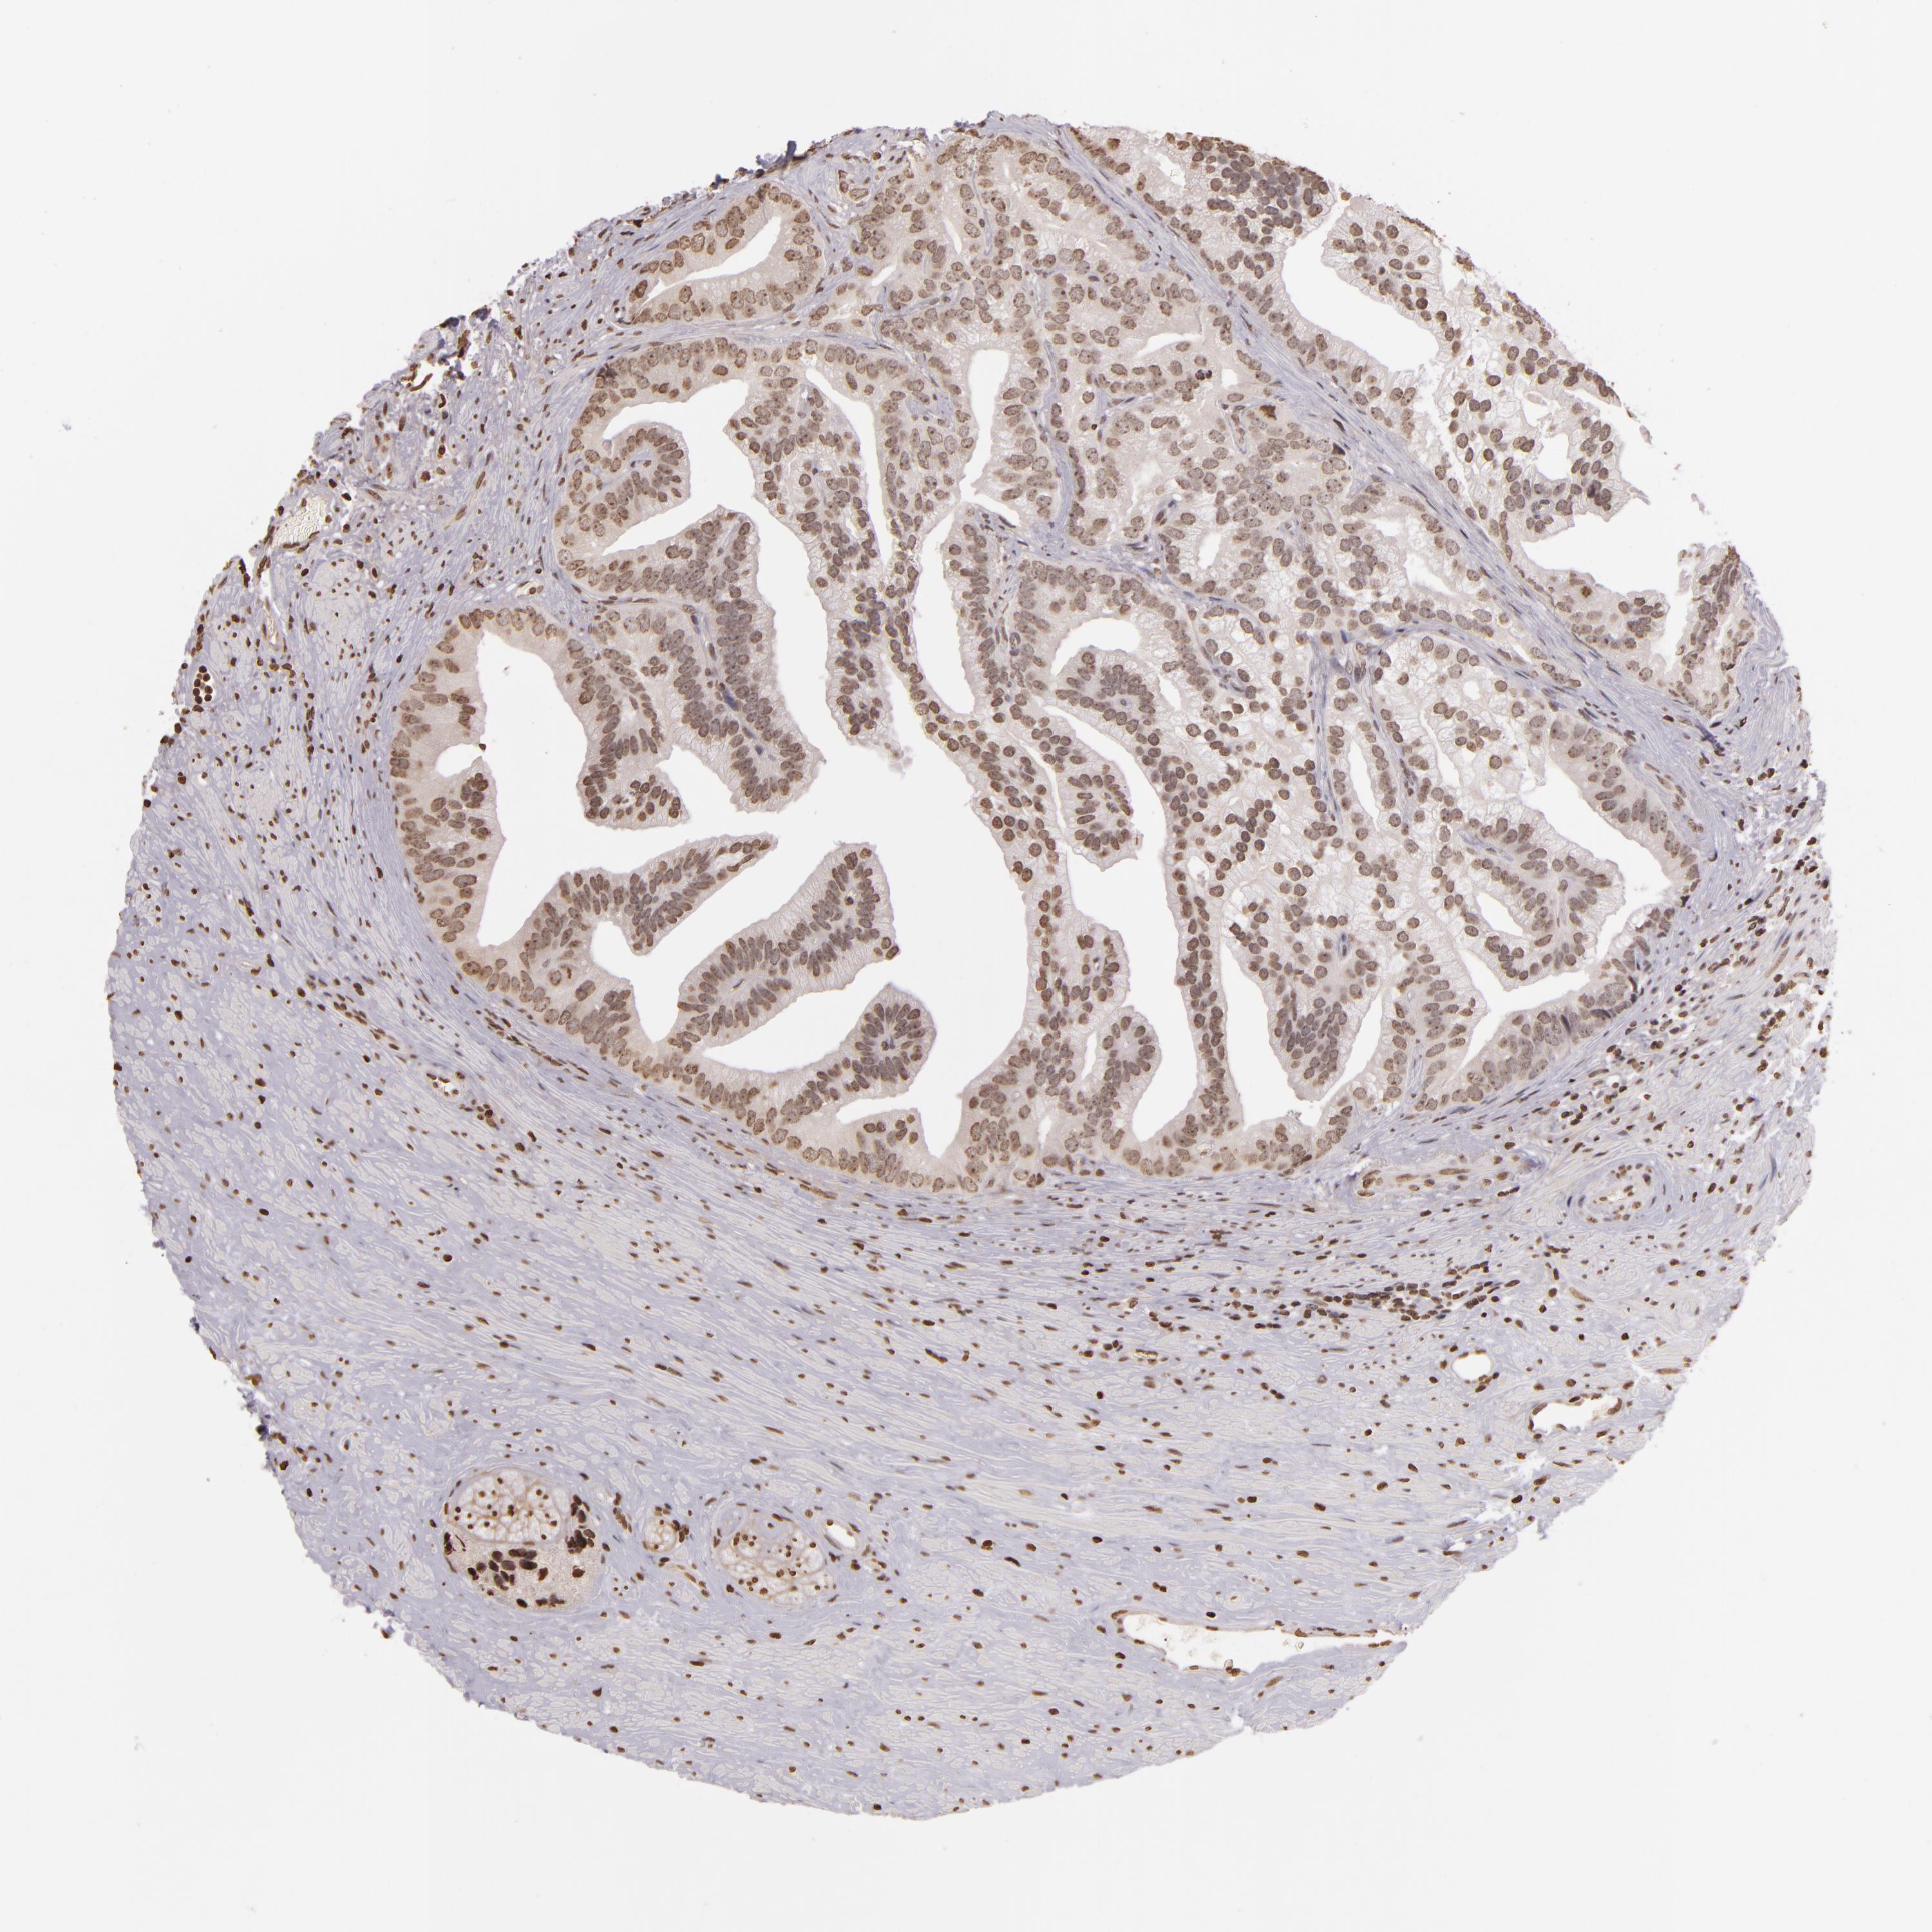

PROSTATE CANCER - Protein expressioni

A mouse-over function shows sample information and annotation data. Click on an image to view it in a full screen mode. Samples can be filtered based on level of antibody staining by selecting one or several of the following categories: high, medium, low and not detected. The assay and annotation is described here.

Note that samples used for immunohistochemistry by the Human Protein Atlas do not correspond to samples in the TCGA dataset.

Antibody stainingi

Antibody staining in the annotated cell types in the current human tissue is reported as not detected, low, medium, or high, based on conventional immunohistochemistry profiling in selected tissues. This score is based on the combination of the staining intensity and fraction of stained cells.

Each image is clickable and will lead to virtual microscopy that enables deeper exploration of all samples and also displays staining intensity scores, fraction scores and subcellular localization as well as patient and tissue information for each sample.

Antibody CAB002008

Antibody CAB002009

Staining

High

Medium

Low

Not detected

Intensity

Strong

Moderate

Weak

Negative

Quantity

>75%

75%-25%

<25%

None

Location

Nuclear

Cytoplasmic/membranous

Cytoplasmic/membranous,nuclear

Adenocarcinoma, Medium grade

Adenocarcinoma, High grade

Adenocarcinoma, Low grade